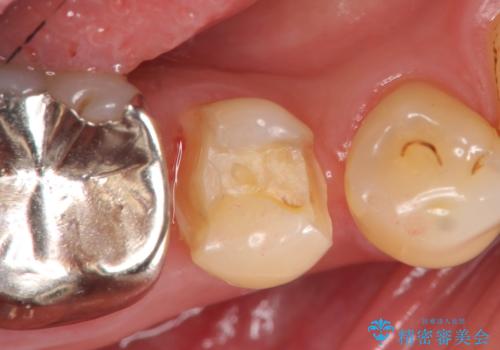

- 右下5番目の歯がしみるので診て欲しいといらっしゃった方の症例です。

古い銀歯及び虫歯を除去後、PGA(ゴールド)インレーによる修復を行いました。